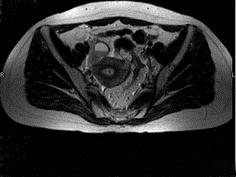

问题 女性,46岁,无任何不适,体检扪及盆腔包块,行MRI检查,如图所示,最佳答案是 ( )

选项 A、卵巢粘液囊腺瘤 B、卵巢结核 C、卵巢皮样囊肿 D、卵巢粘液癌 E、卵巢囊肿

答案 E